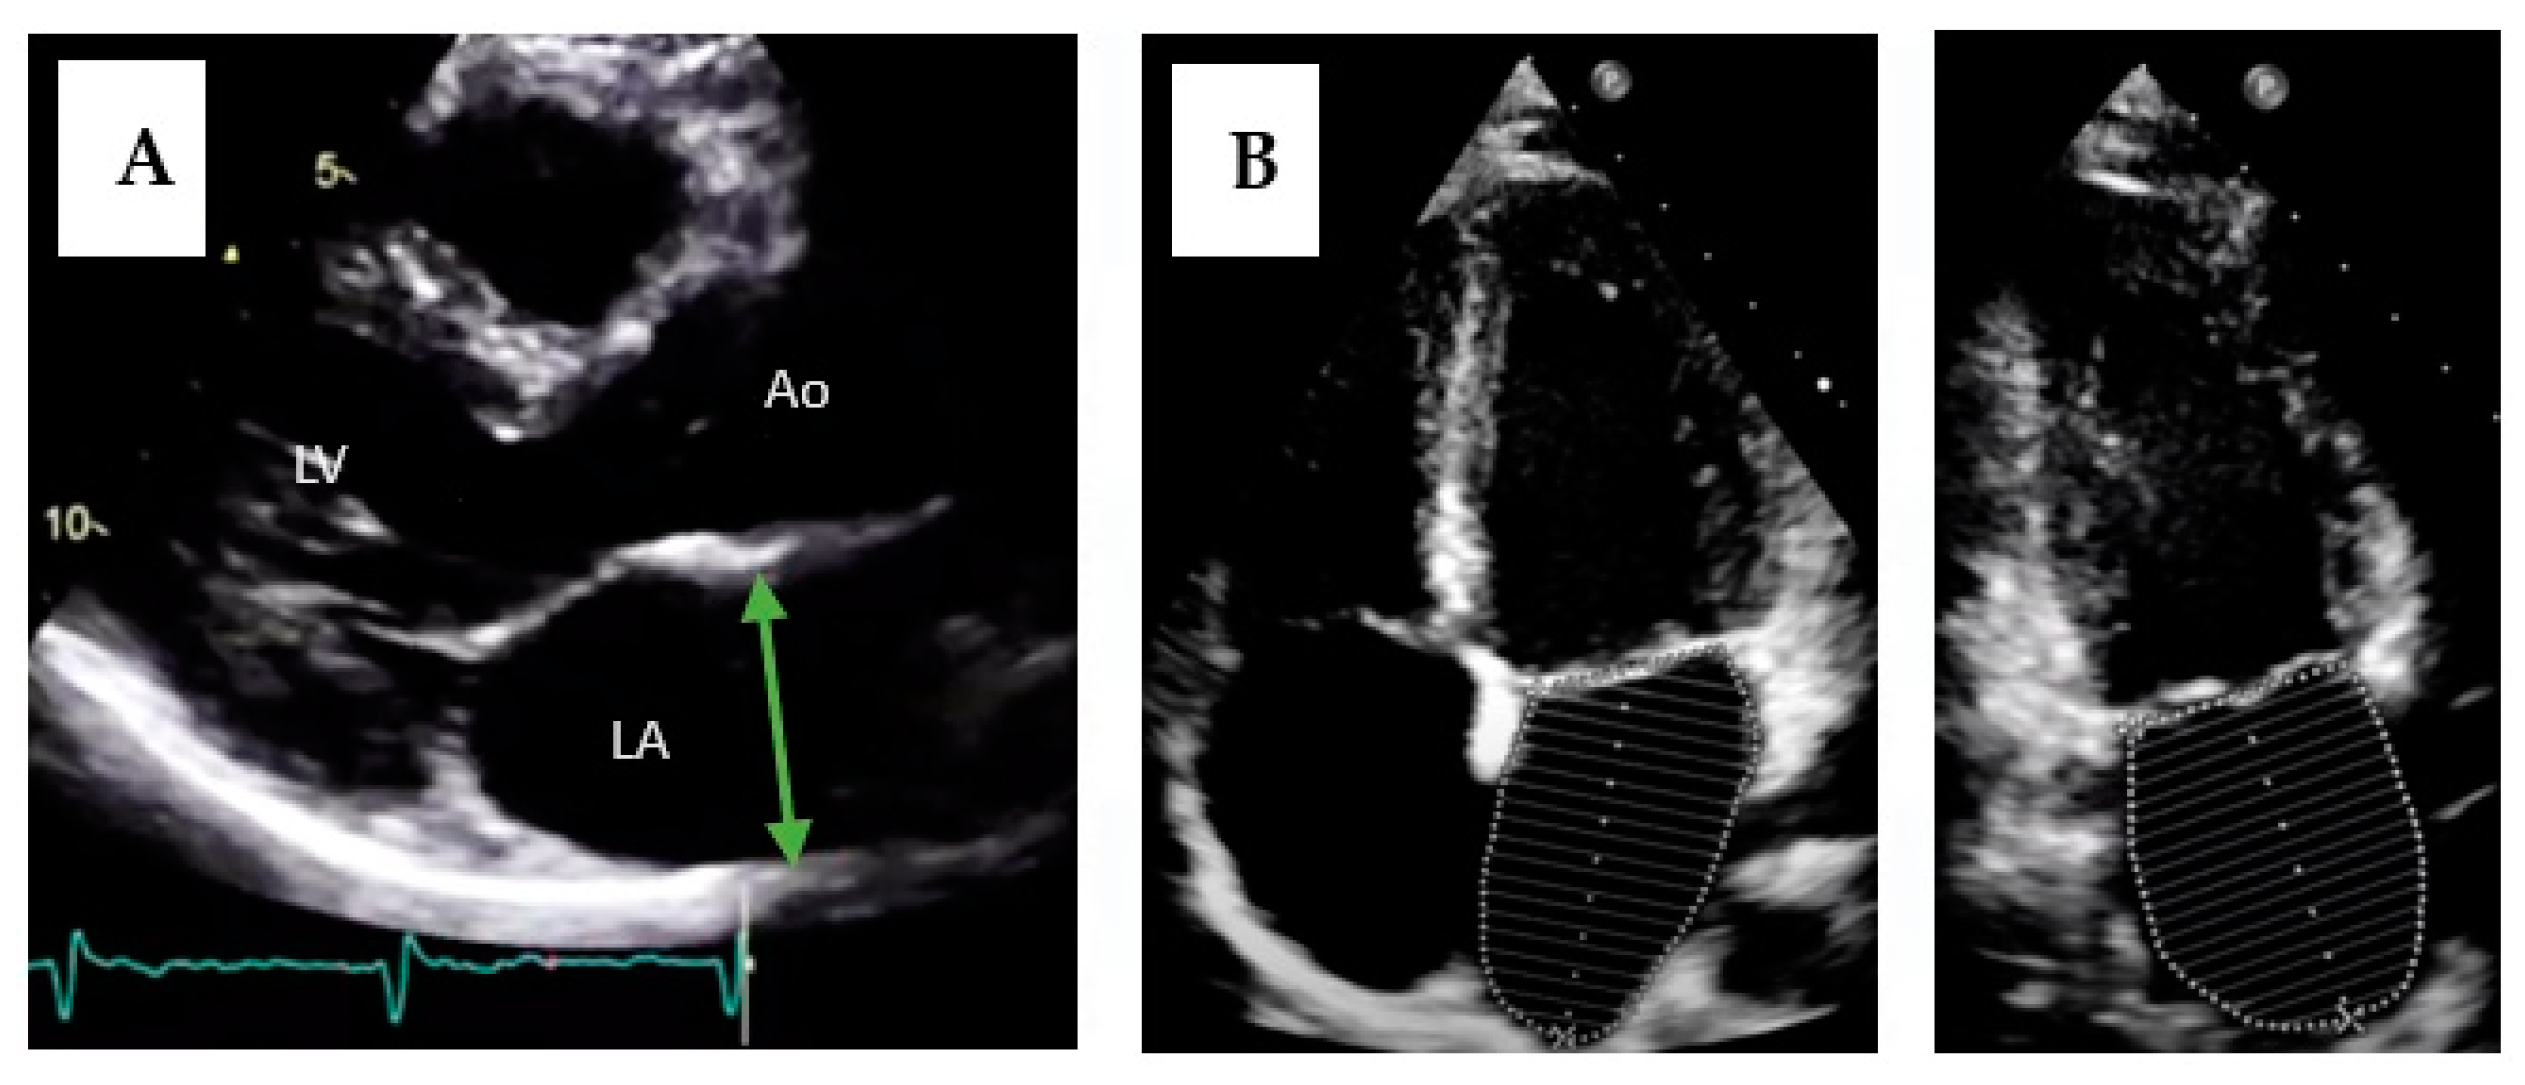

The diagnosis is made with imaging tests, most frequently transthoracic echocardiography, although computed tomography and magnetic resonance imaging are also useful [72]. The most used echocardiographic method was the antero-posterior diameter in a parasternal long-axis view. However, this does not accurately represent atrial size as it assumes that when the atrium grows, it does so equally in all dimensions [73]. Therefore, its isolated use is not recommended. Currently, the most recommended method is left atrium volume measurement, due to its better prognostic value [70,74]. The method of summation of disks in two orthogonal planes (apical two-chamber and four-chamber views) is commonly used, similar to ventricular volumes estimation (Figure 4). Sex difference in atrial size is attenuated when adjusted for body surface area; therefore, it is currently recommended that only indexed measurements should be reported [75]. Although different cut-offs have been used for years, several studies have attempted to establish normal values for left atrial volume, with an indexed volume of 34 mL/m2 being accepted as the maximum normal value [74,75,76].

Figure 4.

Measurement of left atrium size by transthoracic echocardiography. (A) Measurement of the antero-posterior diameter of the left atrium. LA = left atrium; LV = left ventricle; Ao = aorta. (B) Measurement of atrial volume using the disks method in two planes (four-chamber apical and two-chamber apical views).